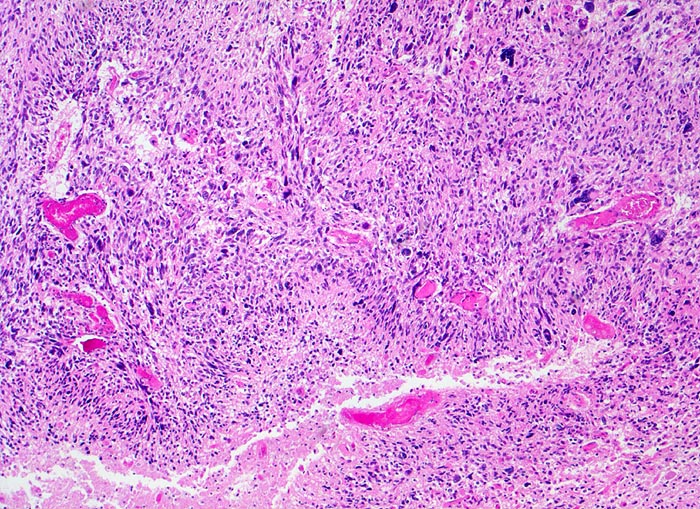

PathoPic ID 5198 - Glioblastoma multiforme (WHO IV)

Glioblastoma multiforme (WHO IV)

maligner Tumor

Hirn temporal

Nervensystem

Zellreicher Tumor mit ausgeprägter Zellpolymorphie und typische streifenförmige

Nekrose.

Seit zwei Monaten zunehmende Persönlichkeitsveränderungen, Kopfschmerzen und progrediente fokal neurologische Zeichen.

Histologie

50

52